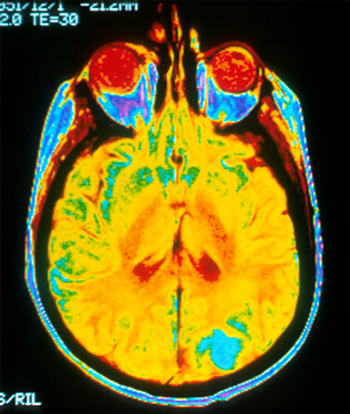

The patient is a 58-year-old woman who was diagnosed at an outside hospital with a World Health Organization (WHO) grade III non–contrast-enhancing right frontal anaplastic astrocytoma, with spread into the genu of the corpus callosum.